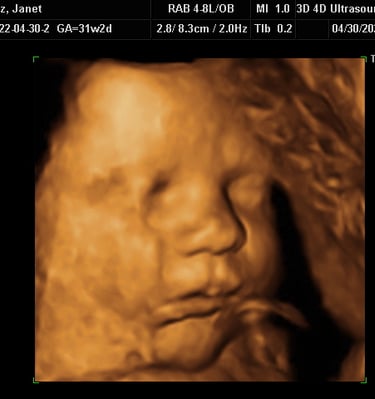

Our Gallery

Explore beautiful moments captured during our 3D and 4D sessions.